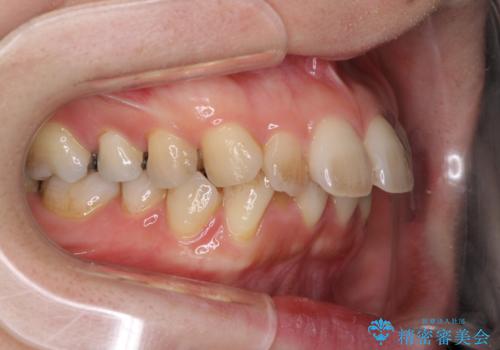

- 上下の出っ歯を気にして来院された患者様です。

口元を積極的に引っ込めるために、上下左右の第一小臼歯を4本抜歯することとしました。

元々ディープバイトのため、スペースを閉じている期間に上下前歯が接触してしまい、治療期間が想定よりも伸びてしまいました。